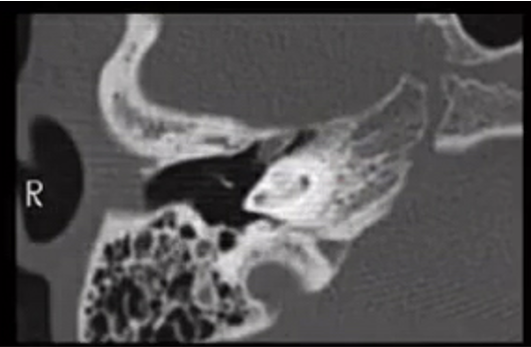

Prolapsing facial nerve (protruding intratemporal facial nerve)

Tubular soft tissue prolapsing into oval window niche from undersurface of LSC. Caused by dehiscence of bony covering of the facial nerve.

No enhancement! If enhances then it is a Schwannoma.

May project into oval indow.